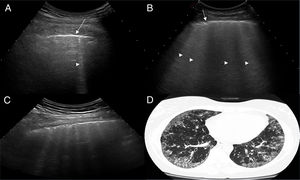

Ultrasound scan interpretationThe basic finding to be evaluated by US is the B line, which is defined as a hyperechoic narrow base reverberation artefact, which extends like a laser beam until the edge of the screen. These B lines are generally not present in the lungs of healthy subjects16,17 (Fig. 1). In each intercostal space (IS) the number of B lines was recorded, and subsequently the total number of all of the B lines found by pulmonary US was registered and classified using the semi-quantitative scale proposed beforehand (0 = normal, ≤ 5 B lines; 1 = mild, ≥ 6 and ≤ 15 B lines; 2 = moderate, ≤ 16 and ≥ 30 B lines; 3 = severe, ≥ 30 B lines). The above operation was performed for the purpose of correlation with HRCT findings.

ResultsA total of 77 patients with a diagnosis of SS were referred to be included in the study. During the recruitment phase no patient gave any reason to suspect pulmonary hypertension. Nine patients were excluded, as they had at least of the exclusion criteria. The study was finally undertaken with 68 patients with SS and 68 healthy controls. A total of 952 IS in 68 patients with SS were examined using pulmonary US. The demographic and clinical characteristics of the study population are shown in Table 1. Twenty eight of the 68 patients (41.2%) showed signs of ILD in US, in contrast with the healthy controls (4.8%) (P = .0001). Fig. 2 shows the different signs of ILD detected by US, including comparative US and HRCT images.

US images showing different signs of ILD based on the number of B lines.

A. There is only one B line (arrowhead). B. 4 B lines are visible (arrowheads). Pleural irregularity is present in both cases (arrows). C. US image showing an intercostal space with 6 B lines and net pleural irregularity in comparison with the HRCT image of ILD (D).